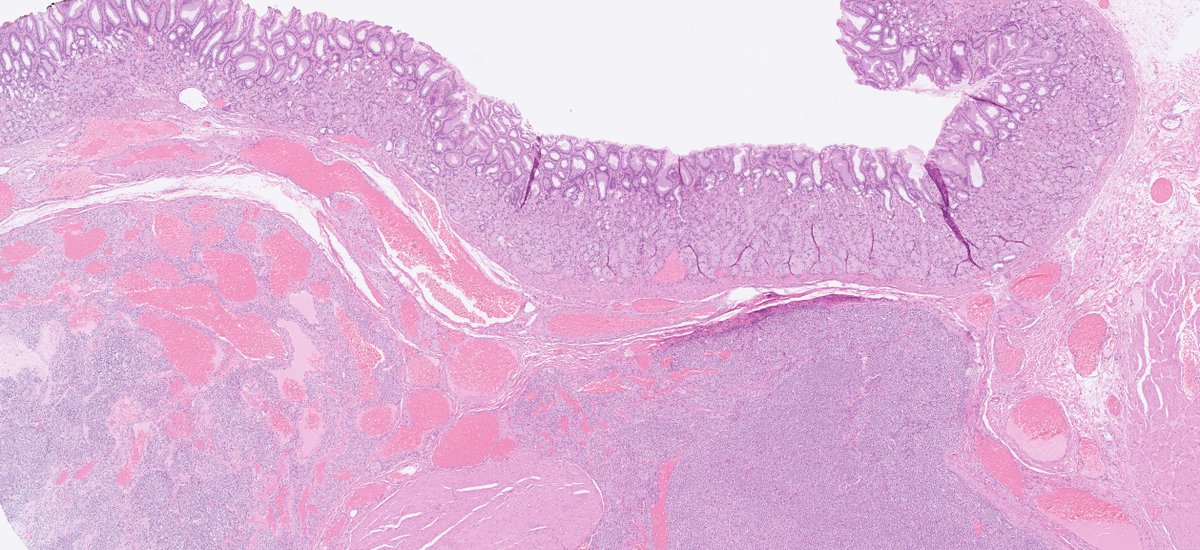

Definitely the best example of ☢️radiation colitis☢️ I've ever seen. Angiectatic vessels are so prominent; they even show superficial thrombi. #GiPath #Pathology

DraEosina's tweet image. Definitely the best example of ☢️radiation colitis☢️ I&apos;ve ever seen.

Angiectatic vessels are so prominent; they even show superficial thrombi.

#GiPath #Pathology